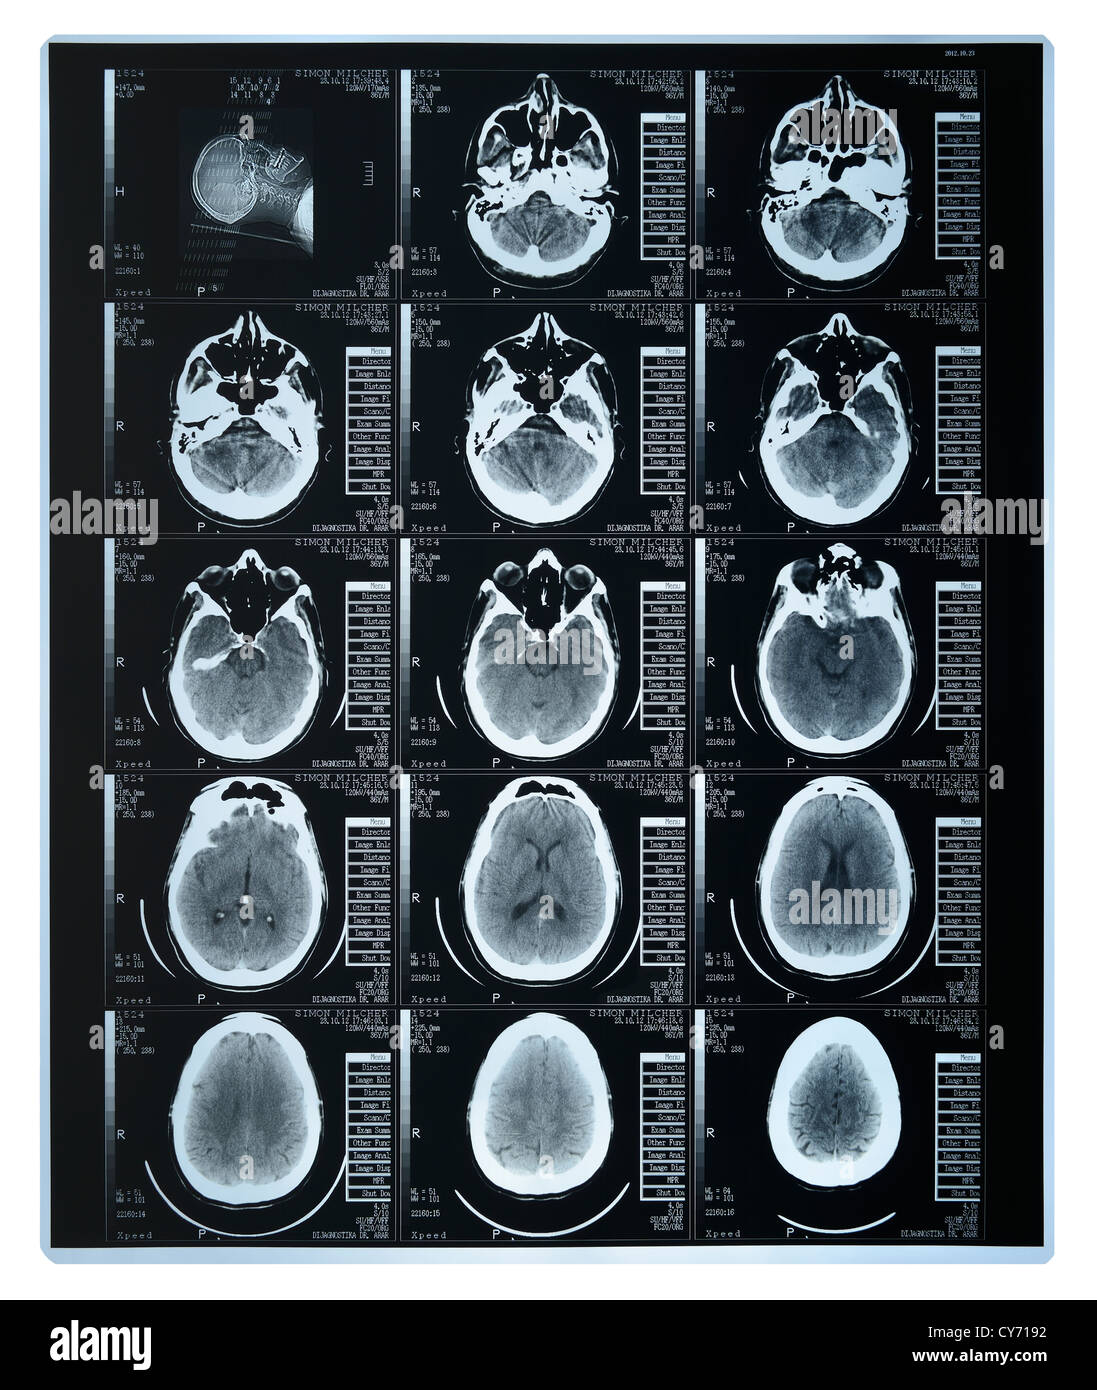

Cat Scan d'un cerveau Banque D'Imageshttps://www.alamyimages.fr/image-license-details/?v=1https://www.alamyimages.fr/photo-image-cat-scan-d-un-cerveau-51171150.html

Cat Scan d'un cerveau Banque D'Imageshttps://www.alamyimages.fr/image-license-details/?v=1https://www.alamyimages.fr/photo-image-cat-scan-d-un-cerveau-51171150.htmlRMCY7192–Cat Scan d'un cerveau